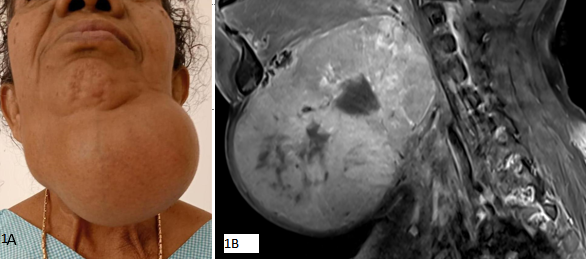

A 64 years old lady presented to the OPD with complaints of a large neck mass in the sub-mandibular region of 20 years duration with a recent rapid increase in size (Figure 1A). Per oral examination showed  lingual thyroid enlargement.

Figure 1

MRI revealed a large mixed-intensity lesion (Figure 1B) involving the base of the tongue and floor of the mouth, measuring approximately 9.2 cm anteroposteriorly (AP) × 10.7 cm transversely (TR) × 11.1 cm craniocaudally (CC).The lesion is seen extending exophytically into the neck region with a predilection towards left side. Visualised lung fields show multiple T2 hyperintense nodules on both sides likely metastasis. Thyroid is not visualized in the thyroid fossa-likely absent.